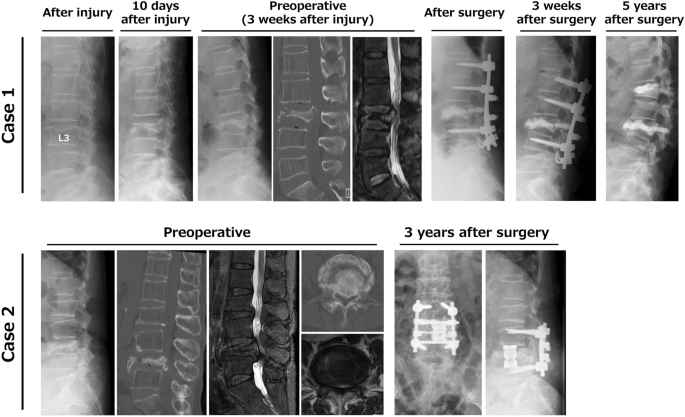

PD is a systemic and progressive disease, which suggests that the natural course of PD should be considered in treatment for OVC in a patient with PD. These aspects of PD might also influence clinical features and imaging findings in OVC. In the classification of OVC based on preoperative lateral radiographs, flat-type (type 2) low lumbar OVC was dominant in non-PD cases, whereas destructive-type (type 4) was found in most PD cases. The main clinical symptom in type 2 low lumbar OVC is radicular pain resulting from retropulsed bony fragments causing foraminal stenosis and/or canal stenosis2. In contrast, rapidly progressive OVC in type 4 could lead to cauda equina symptoms due to rapid and severe spinal canal stenosis. In addition, old compression fracture at the thoracolumbar level was found in most non-PD cases, but in few PD cases. Spinal alignment changes may increase middle and/or posterior low lumbar spine loading, and lower bone quality and severe sarcopenia in PD might cause rapid progression and destructive changes of OVC (Fig. 2).

Differences in the pathomechanism of low lumbar osteoporotic vertebral collapse (OVC) in patients with or without Parkinson’s disease (PD). (A) OVC is most frequent at the thoracolumbar junction, such as at T12 and L1, due to anterior loading on the spine. (B) Most non-PD cases have old thoracolumbar compression and decreased lumbar lordosis (L1-S1). (C) Most patients with PD have decreased lumbar lordosis without old thoracolumbar compression. Cases with decreased lumbar lordosis (B, C) have increased middle and/or posterior loading on the low lumbar spine after changes in spinal alignment.